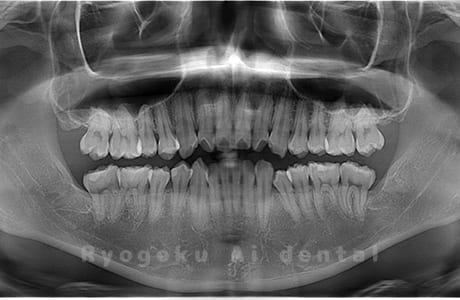

Case04

-

- 原因

- 上顎の親知らず、下顎の水平埋伏の親知らず

- 治療内容

- 上顎の親知らず、下顎の水平埋伏の親知らずを抜歯したケースです。

<リスク・副作用>

手術後は痛み、腫れ、痺れなどの副作用が生じる場合があります。